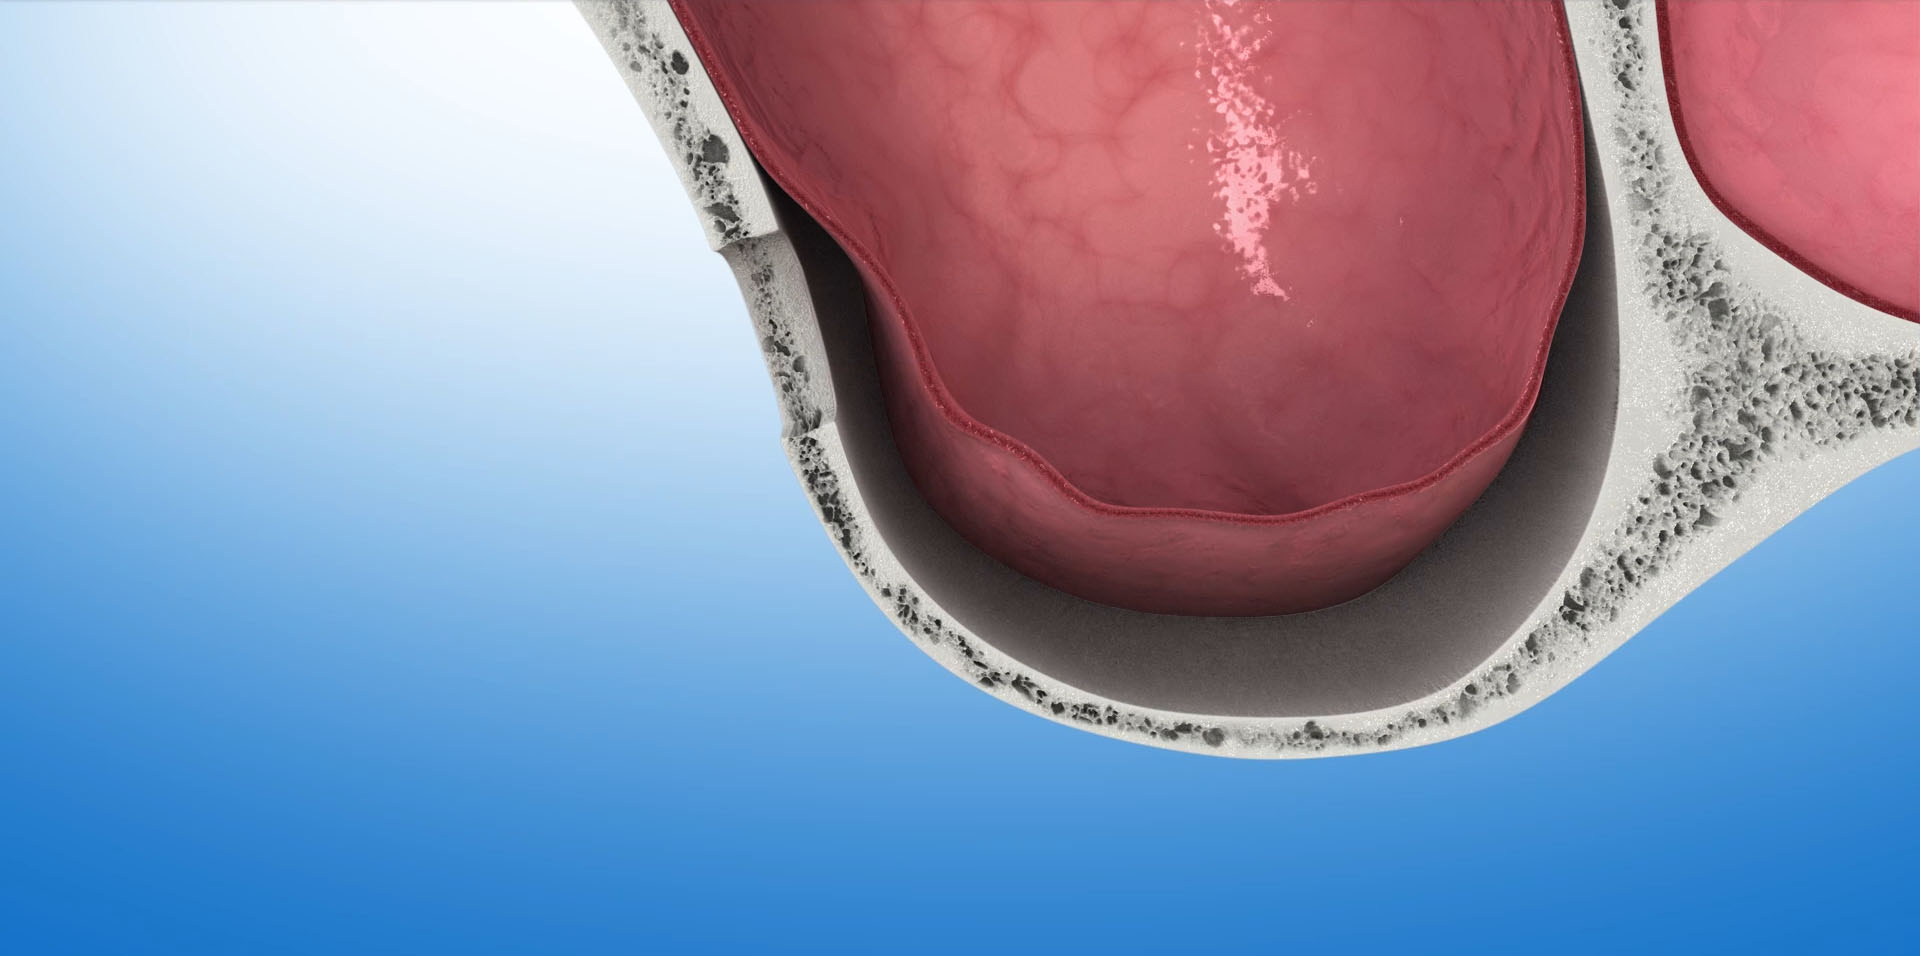

Miejscem, w którym bardzo często spotykamy się z deficytem kości uniemożliwiającym implantację są tylne obszary szczęki górnej. Powodem tego jest znajdująca się po obu stronach trzonu szczęki – zatoka szczękowa (sinus maxillaris). Jest to wypełniona powietrzem przestrzeń w kształcie trójściennej piramidy, której podstawa skierowana jest do dołu. W trakcie życia objętość zatoki powiększa się – następuje jej pneumatyzacja. Utrata zębów w obszarze znajdującym się bezpośrednio pod zatoką szczękową, następujący w związku z tym zanik kości oraz postępująca pneumatyzacja bardzo często uniemożliwia bezpośrednią implantację. Musi być ona poprzedzona zabiegami odbudowującymi kość.

Zabiegiem operacyjnym, którego efektem jest odbudowa kości umożliwiająca implantację w tej okolicy szczęki jest- podniesienie dna zatoki szczękowej -sinus lift. Przeprowadzony po raz pierwszy w 1975 roku, dzisiaj jest bardzo bezpiecznym i przewidywalnym zabiegiem, dającym bardzo dobre wyniki w leczeniu implantologicznym. W zależności od stopnia zaniku tkanki kostnej, która znajduje się pomiędzy zatoką szczękową a jamą ustną zabieg podniesienia dna zatoki szczękowej wykonywany jest dwoma metodami: otwartą lub zamkniętą.

Podniesienie dna zatoki szczękowej metodą otwartą

Polega na wycięciu w bocznej ścianie zatoki małego okienka, przez które narzędziami ultradźwiękowymi i ręcznymi delikatnie odwarstwiamy błonę śluzową zatoki od kości dna zatoki. W uzyskaną przestrzeń aplikujemy materiał kościotwórczy. Okienko pokrywamy membraną zaporowa i zamykamy dostęp do zatoki. Tą metodą możemy uzyskać nawet ponad 10mm nowej kości, która umożliwi nam implantację w tym obszarze. Po zabiegu następuje okres regeneracji kości, w czasie którego wprowadzony biomateriał zamienia się w tkankę kostną. W zależności od ilości użytego biomateriału i stopnia podniesienia dna zatoki okres ten może trwać od 6 do 12 miesięcy.